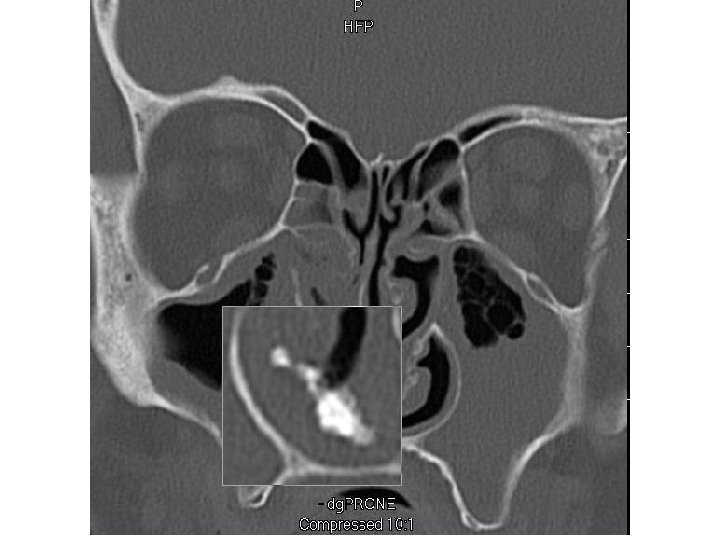

Ethmoid Sinusitis

Coronal computed tomographic scan showing ethmoidal polyps. Ethmoid opacity is total as a result of nasal polyps, with a secondary fluid level in the left maxillary antrum.